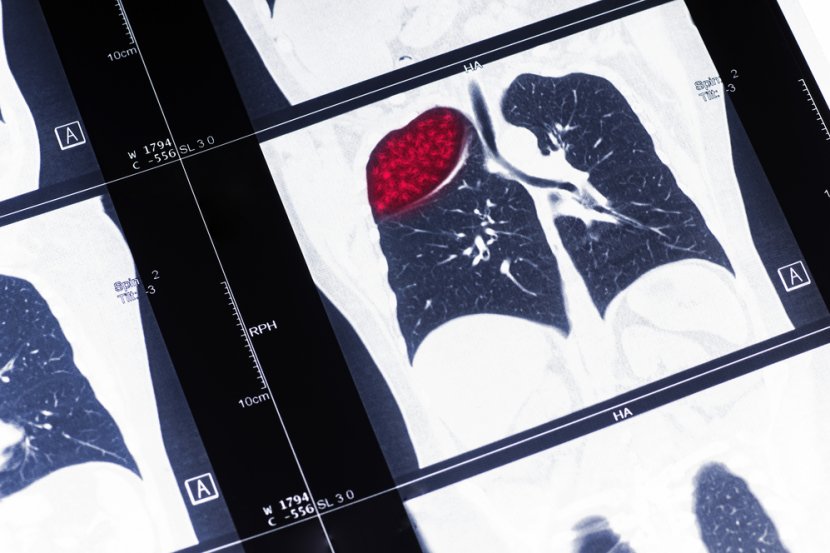

Zašto je opasno da pacijent koji ima rak pluća propušta tretmane zračenjem

Idealno je da pacijent sa rakom pluća obavi lečenje onako kako je propisano i da ne propusti nijedan dan terapije. Ali, ako se desi da preskoče neki dan, lekari onda primenjuju drugi "recept"

Dok lekari rade na razvoju personalizovanije nege ljudi obolelih od karcinoma, nova studija Fox Chase Cancer Center u Filadefiji bavi se pitanjem da li pacijenti koji imaju rak pluća mogu da propuste nekoliko dana tretmana zračenjem i da ih zatim nadoknade većom dozom.

Pacijent koji ima rak pluća rizikuje raniju smrt ako preskače terapije

Prema istraživanju filadelfijskog centra za rak, što više tretmana pacijent preskoči, to je veći rizik od rane smrti. Međutim, neki pacijenti, kako kažu istraživači, mogu i dalje da imaju koristi od primanja većih doza zračenja ako propuste tretmane.